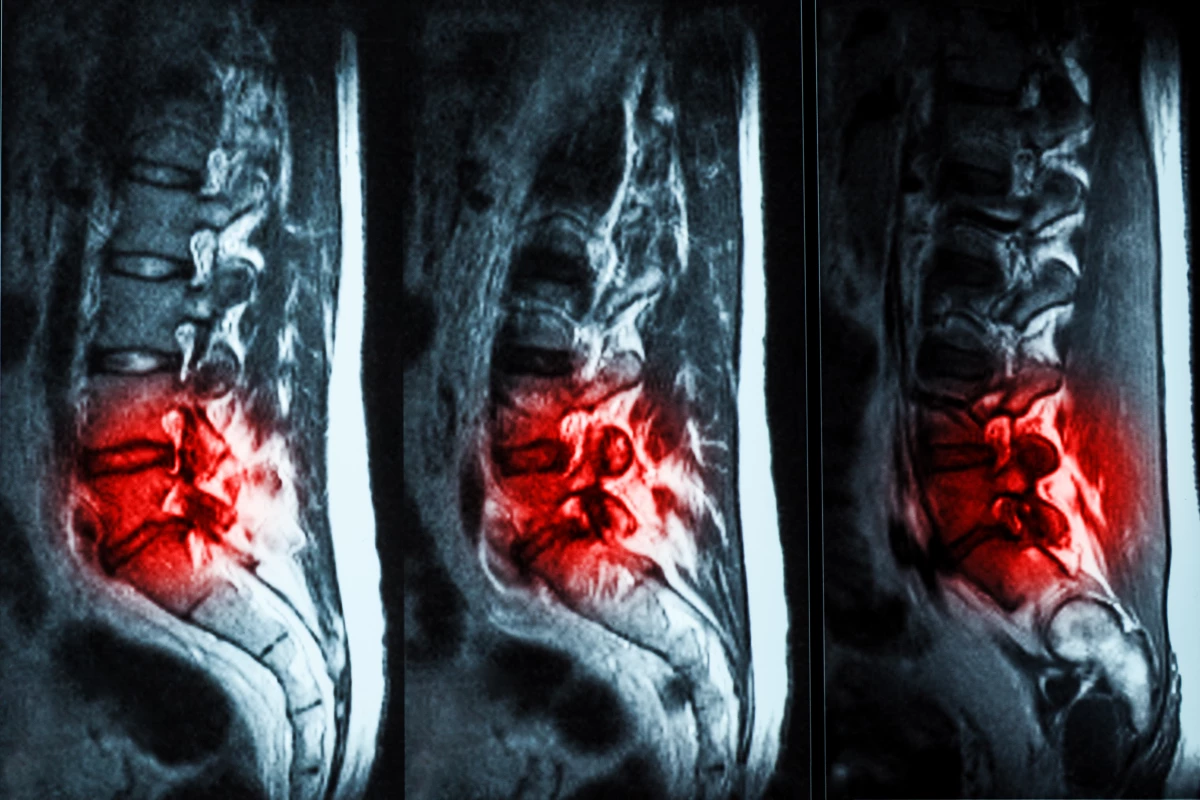

An injectable hydrogel has shown promise in repairing damaged spinal discs in a new human trial

Human trials have shown that hydrogel injections are a promising, effective treatment for chronic lower back pain caused by degenerative disc disease (DDD). The treatment is far less invasive than other surgeries, and has been given FDA approval.

Spinal discs play an important role in cushioning the vertebrae, but as with many parts of the body they begin to wear out with age. In many people, the fluid filling of the discs can dry up or leak out, causing pain and affecting mobility. Unfortunately, treatments are largely limited to care like rest, physical therapy and painkillers, or in more severe cases, surgery where discs are removed or replaced with prosthetics.

But recently, scientists have developed a new option – a hydrogel that can be injected into the spine where it fills in cracks and tears in the affected disc, restoring some of its cushioning to alleviate pain. Developed by the medical company ReGelTec, the gel is known as Hydrafil, and in 2020 it received a Breakthrough Device designation from the US FDA. And now the results of the first human trials are in.